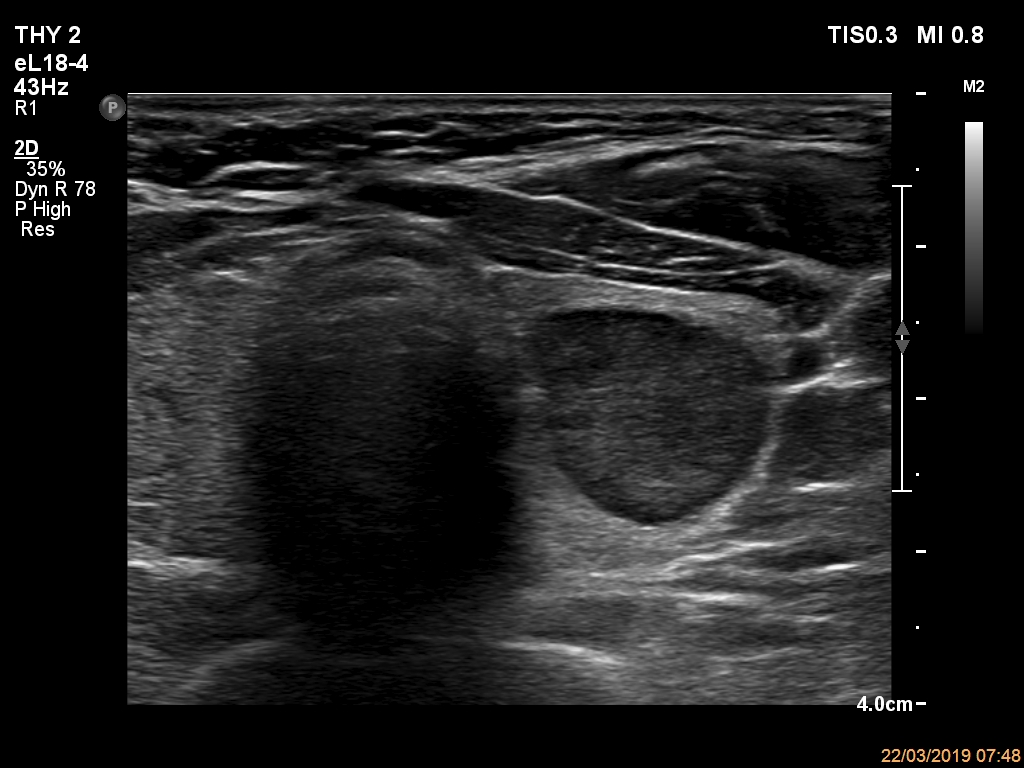

Ultrasonography. The thyroid was echonormal and had multiple nodules. The only lesion of a possible oncological importance was in the left lobe. It was hypoechoic. The dimensions were 16x14x23 mm (width, depth, length, respectively). The lower border presented an undulation which was caused by another, hyperechoic nodule. The nodule presented a predominant perinodular blood flow and had an average rigidity on elastography.

The nodule in the left lobe illustrates non-pathological form of lobulated margins.